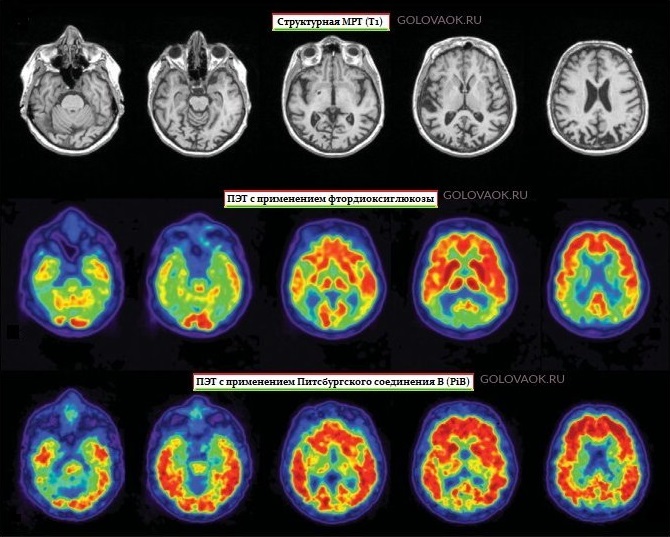

Что такое диффузная атрофия

Что такое диффузная атрофия 114 фотографий